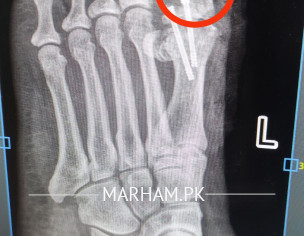

Talk to Orthopedic Surgeon on Post Operation X-ray

AoA, kindly ye meri mother ki xray report daikh kar bta dain k operation theek ho gya hai, X-ray main fracture nazar aa rha hai lekin, technician ny b kaha k fracture show ho rha hai kisi doctor ko dikha dain. shukria

Better to consult your treating surgeon again please.

Thank you

Need following informations

1- Date of injury or weeks

2- XRay before Surgery

3- XRay just after surgery

4- XRay latest , you already shared

Regards

get examined by surgeon for complete history and details regarding surgery.

Osteotomy means cutting the bone to straighten it, usually to relieve pain or improve joint function. After the cut, the bone is held in place with plates, screws or pins while it heals. Most people need a period of limited weight‑bearing followed by physical therapy to rebuild strength and range of motion. Recovery can take several months, and the goal is to return to normal activities, but some patients may still need braces or activity adjustments. The procedure is common for knee, hip or foot problems, and outcomes are generally good when the surgeon’s plan matches the patient’s anatomy and the rehab is followed closely. If you’re considering it, talk to an orthopedic surgeon about your specific condition, the expected healing time, and any lifestyle changes that will help you recover fully.